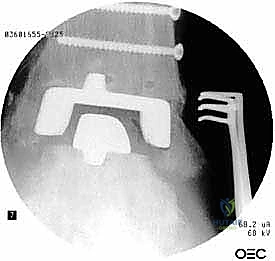

خطوات جراحة مراجعة مفصل الكاحل (Agility) بالتفصيل

تعتبر غرفة العمليات ساحة لإظهار البراعة الجراحية. عملية المراجعة تستغرق عادة من 3 إلى 5 ساعات وتتم عبر الخطوات المعقدة التالية:

الخطوة الخامسة: تركيب المفصل الجديد أو الدمج

يتم إدخال المفصل الجديد المخصص للمراجعة، والذي يحتوي غالباً على سيقان (Stems) تدخل عميقاً في عظمة الساق وعظمة الكاحل لضمان الثبات الميكانيكي. في حال وجود كسور في الكعب، يتم تثبيتها في هذه المرحلة.